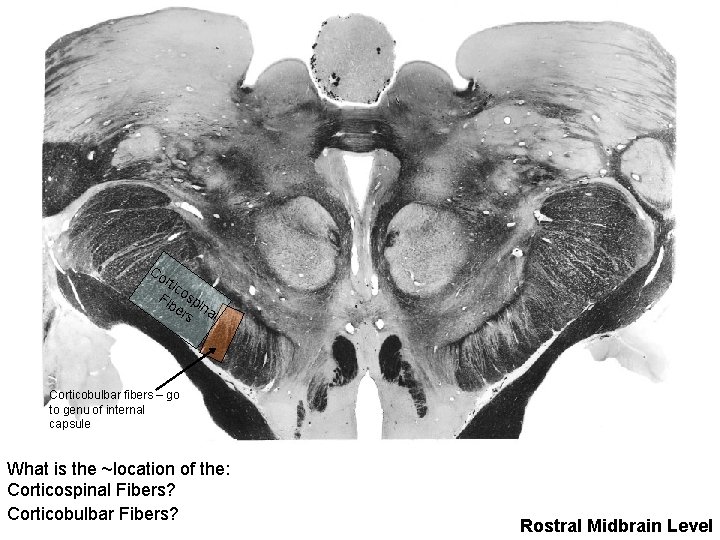

Co rtic Fib osp er ina l s Corticobulbar fibers – go to genu of internal capsule What is the ~location of the: Corticospinal Fibers? Corticobulbar Fibers? Rostral Midbrain Level